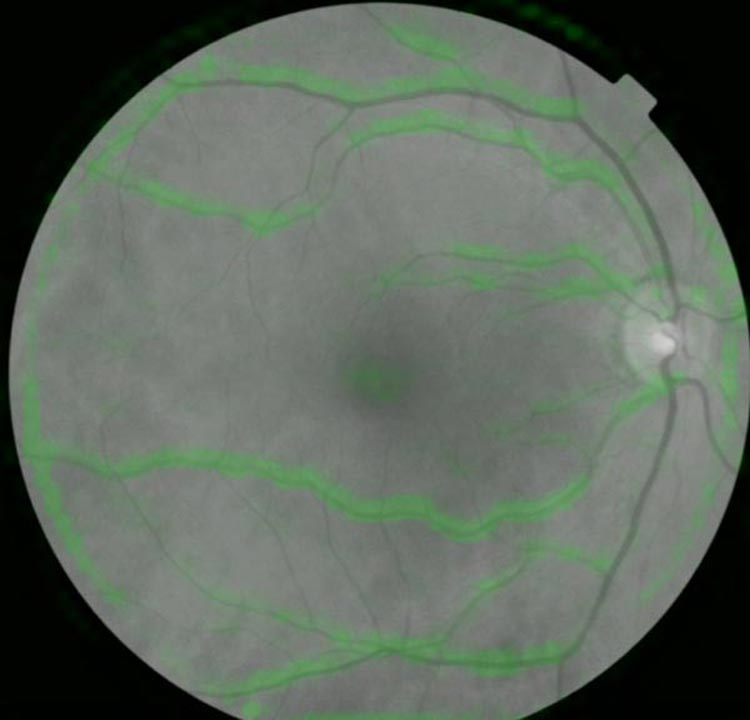

রেটিনা।

রেটিনা এমন দেখতে হলে ৫ বছরের মধ্যে হার্ট অ্যাটাকের সম্ভাবনা যথেষ্টই

বরদারাজন বলছেন, ‘‘ডায়াবেটিস, উচ্চ রক্তচাপের মতো এ ক্ষেত্রেও রেটিনার রক্তনালীগুলির চেহারা, চরিত্র, আচার-আচরণ দেখে হার্ট অ্যাটাকের পূর্বাভাস দেওয়া সম্ভব হবে।’’

বিশিষ্ট চক্ষু বিশেষজ্ঞ হিমাদ্রি দত্তের কথায়, ‘‘রক্ত শরীরে কী ভাবে বইছে, তার জন্য শিরা ও ধমনীর কী কী পরিবর্তন হচ্ছে, তার উপর নজর রেখেই বিভিন্ন রোগ শরীরে বাসা বেঁধেছে কি না, করলে তা কতটা আগ্রাসী ভূমিকা নিয়েছে বা নিতে পারে তা আন্দাজ করা যায়। কারণ, সে ক্ষেত্রে রক্তনালীগুলি স্বাভাবিকের চেয়ে বেশি সরু বা শক্ত হয়ে যায়। আর সেটা চোখের রেটিনাতেই সবচেয়ে ভাল ভাবে ও সবচেয়ে সহজে বোঝা যায়। তাই এই পদ্ধতি আগামী দিনে হার্ট অ্যাটাকের পূর্বাভাসে যথেষ্টই সাহায্য করবে।’’

বিশিষ্ট চক্ষু বিশেষজ্ঞ অসিত রঞ্জন বন্দ্যোপাধ্যায়ের বক্তব্য, ডায়াবেটিস হলে বা রক্তচাপ বাড়লে দেহের অন্যান্য অংশের মতো রেটিনার রক্তনালীগুলিও ফুলে যায় বা ‘হেমারেজ’ হয় (রক্তনালীগুলি ছিঁড়ে যায়)। অনেক সময় রেটিনার মাঝামাঝি এলাকায় সাদা দাগও দেখা যায়। এটাকে বলে ‘এক্সুডেট’। কখনও বা হয় ‘মাইক্রো-অ্যানিউরিজম’। সে ক্ষেত্রে রক্তনালীগুলি ফুলে উঠে গোল গোল হয়ে যায়। কোলেস্টেরলের মাত্রা শরীরে বেড়েছে কি না, তা এই ভাবে রেটিনার রক্তনালীগুলি দেখে বোঝা যায়। তবে ওই রোগগুলির পূর্বাভাস ৫ বছর আগে দেওয়া সম্ভব হয় না রেটিনা দেখে। কিন্তু এই পদ্ধতি পূর্বাভাস দিতে পারবে হার্ট অ্যাটাকের, ৫ বছর আগে। এটাই এই পদ্ধতির অভিনবত্ব। তবে আরও পরীক্ষানিরীক্ষার প্রয়োজন রয়েছে। দেখার আছে, বয়স বাড়ার সঙ্গে সঙ্গে এই ‘অ্যালগরিদম’ কতটা মানানসই হয়।